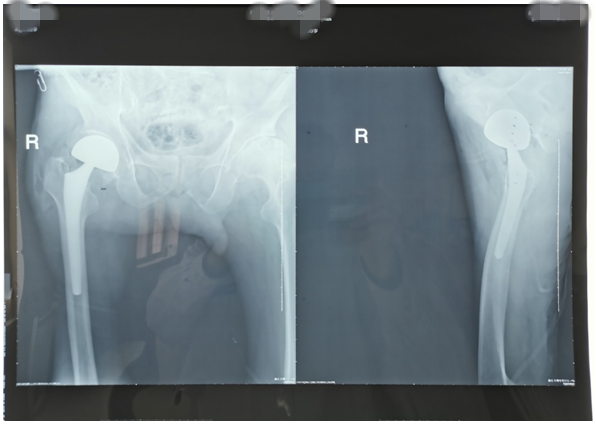

近期,我科又為兩位高齡老人因股骨頸骨折行髖關(guān)節(jié)置換術(shù)。一位是呂大爺,82歲高齡,右髖部外傷后疼痛一個月就診。當時呂大爺外傷后局部疼痛,未引起注意仍日常活動,癥狀逐漸加重后就診,既往有高血壓、腦梗塞、腦出血病史,入院后積極完善術(shù)前評估,在無絕對手術(shù)禁忌癥時行右側(cè)股骨頸骨折髖置換術(shù),手術(shù)時間短,出血少,術(shù)后第二天呂大爺扶助步器下床活動,避免了因骨折長時間臥床各種并發(fā)癥的發(fā)生,老人及家屬對我們的治療非常滿意。(見下圖)

右髖正側(cè)位手術(shù)前后對比圖